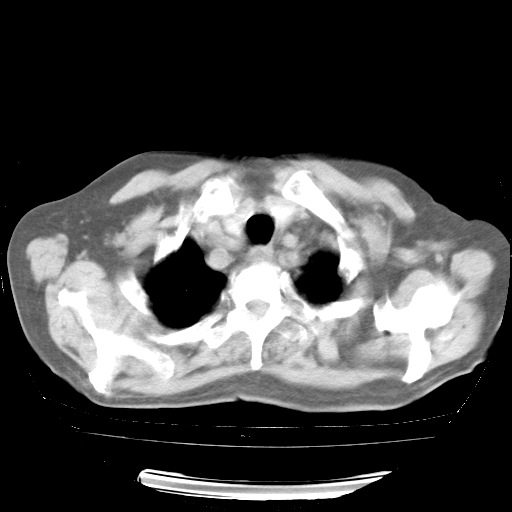

4月28日肺部CT